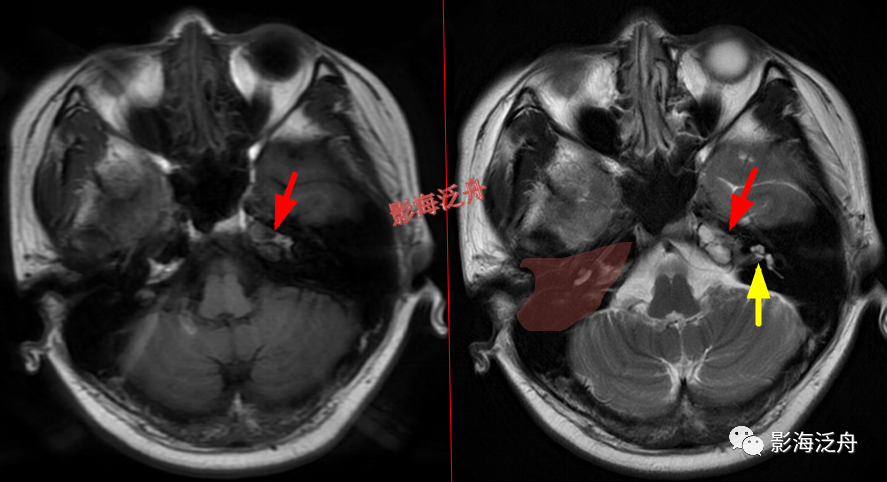

颅骨病变

左侧岩尖部囊性病变(红箭头),患者未术,病理不明。MR对骨质结构显示不佳,因此很多读者会忽略掉颅内骨质病变的观察,很多颅内病变,如三叉神经鞘瘤、鼻咽癌

等都会造成颞骨岩部(红色标注区)骨质破坏,因此,平时应对此处多加留意。黄箭头指听神经及内耳结构。

蝶骨骨纤维异常增殖症(红箭头),病灶内部可见特征性的囊变区(黄箭)。蝶骨的病变在MR上识别起来更为困难,因为蝶骨位于颅底部,此处骨骼、肌肉、脂肪等多种组织成分混杂,导致正常情况下也看起来非常乱。不要着急,慢慢学。